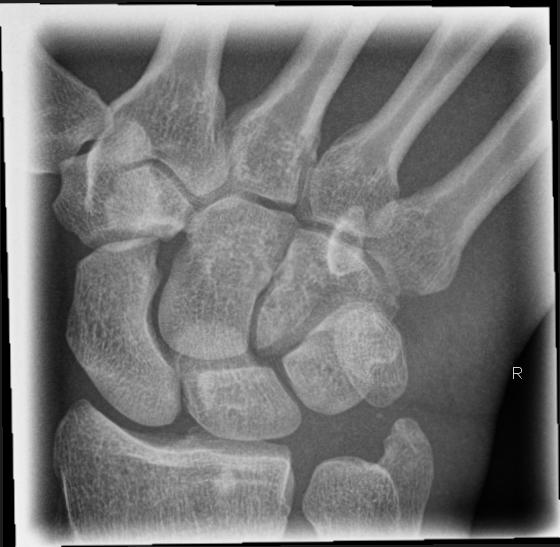

Handgelenk dorso-volar (1. Ebene)

Technik

• FDA: 1,05 m

• Ausgangsformat: 18/24

• Übertischaufnahme

Indikation

Fraktur

Lagerung

sitzend - seitlich zum Tisch

abgewinkelter Unterarm und die Handfläche liegen auf

Finger 2-5 werden leicht aufgestellt

Zentralstrahl

senkrecht

Querzentrierung auf Gelenkspalt

Längszentrierung auf Objektmitte

Einblendung

distal einschließlich Fingergrundgelenke

Anmerkung

Darstellung der Handwurzel- und Unterarmknochen, bei Fragestellung von Epiphysenlösung, Grünholz- oder Os scaphoideumfraktur. Zur Beurteilung der Knochenkerne bei Kindern werden Vergleichsaufnahmen notwendig, bei Verdacht auf Subluxation des Os Lunatums, Zusatzaufnahme in Flextion und Reflextion der Hand notwendig (siehe Stressaufnahme).

ggf. Tisch hochfahren

Qualitätskriterien

Vollständige Abbildung der Metacarpalia, Handwurzelknochen und distaler Unterarm.